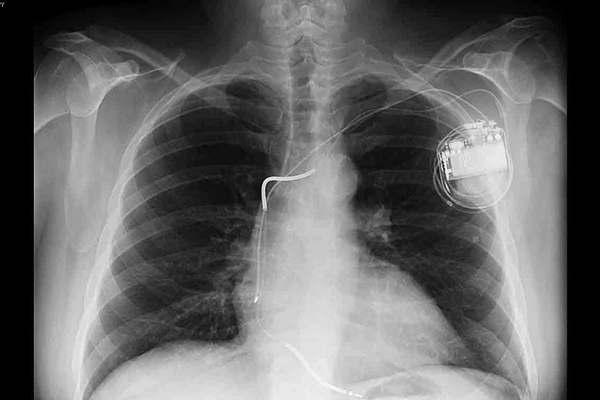

En un acontecimiento inédito para Añatuya y zonas de influencia, un centro de salud privado realizó por primera vez un implante de un marcapasos.

Los responsables de la clínica destacaron que se trata de una práctica que se realiza en el mundo hace más de medio siglo. Concretamente es una intervención que, por medio de un dispositivo, permite realizar descargas eléctricas al corazón cumpliendo funciones como sincronizar por problemas de comunicación entre un ventrículo y una aurícula; ayudar a evitar problemas de ritmos cardíacos; mejora de la función de bombeo del corazón; etc.

El hecho se dio el viernes 29 de septiembre, en la ciudad de Añatuya, siendo que se realiza el primer implante de marcapasos en la ciudad y zonas de influencia. En este caso beneficiando a un afiliado del Pami, de sexo masculino, de 72 años, de la localidad de Los Juríes.